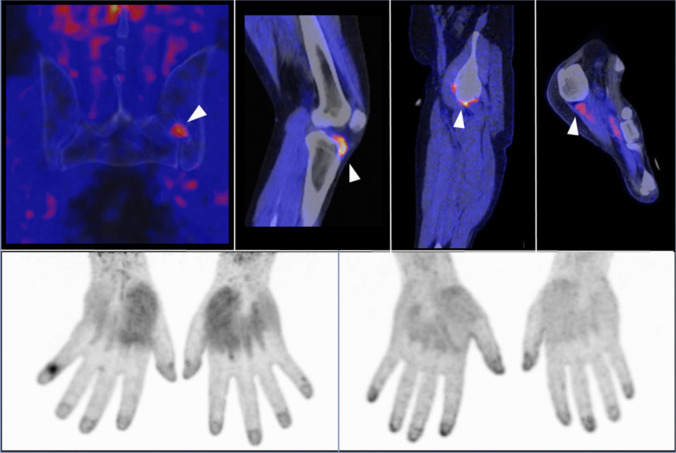

Purpose of review: Psoriatic arthritis (PsA) is a complex heterogeneous inflammatory disease that affects about one-third of patients with psoriasis. PsA leads to significant physical impairment and reduced quality of life. Therefore, early diagnosis and intervention are critical for improving long-term outcomes. The purpose of this review is to highlight the advantages of unconventional imaging methods in the diagnosis and management of PsA and to discuss recent advancements in imaging technology.

Recent findings: Conventional imaging methods, such as radiography, musculoskeletal ultrasound, and magnetic resonance imaging, have been instrumental in detecting structural joint damage and inflammation. However, these imaging modalities have several limitations, resulting in their inability to detect early disease changes. Recent advancements in imaging technology have led to the development of novel imaging modalities capable of characterizing not only early structural but also molecular aspects of disease activity. These cutting-edge approaches have been lately applied to both psoriasis and PsA patients, offering new insights into disease progression, the transition from psoriasis to PsA, and treatment responses. By providing more detailed and individualized assessments, unconventional imaging modalities may bring us closer to realizing the potential of personalized medicine in the management of PsA.